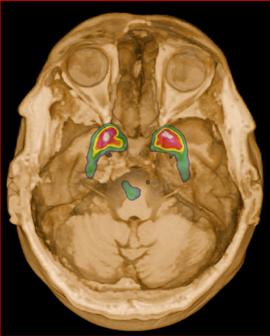

Femenino de 65 años, antecedente de hipertensión arterial de 20 años de evolución en control. Sin antecedentes familiares relevantes de enfermedades neurológicas. Acudió a consulta médica por deterioro progresivo en su capacidad motora y dificultades en las actividades diarias. Desde hace 2 años ha notado cambios en su marcha y en su habilidad para realizar movimientos finos con las manos principalmente del lado izquierdo, rigidez muscular, temblor en reposo siendo mayor del lado izquierdo y dificultad para iniciar y mantener el movimiento, especialmente al levantarse de una silla o al comenzar a caminar. Además, los familiares han observado que tiene una expresión facial inexpresiva y que su voz se ha vuelto más monótona. A la exploración física con expresión facial inexpresiva, temblor de reposo bilateral en manos de predominio izquierdo, rigidez muscular generalizada, más pronunciada en las extremidades superiores, bradicinesia evidente en la realización de movimientos finos de las manos, marcha festinante con pasos cortos y arrastrando los pies, reflejos osteotendinosos normales, no se observan déficits sensoriales. Se realiza adicionalmente la escala de Evaluación de la Enfermedad de Parkinson (UPDRS) con un total de 35 puntos, indicando moderada afectación de la enfermedad. Inicialmente se realiza una tomografía simple de cráneo, sin alteraciones estructurales, al no encontrar algún hallazgo se decide realizar posteriormente Resonancia Magnética Cerebral 1.5 Tesla: sin alteraciones estructurales significativas. Por este motivo y ante la alta sospecha clínica se realiza estudio de imagen molecular PET-RM con 6-[18F] FDOPA en equipo 3 Tesla en el cual se observa la disminución de la captación de la 6-[18F]FDOPA a nivel de putamen y caudado de predominio derecho evidenciando la degeneración dopaminérgica nigro presináptica a este nivel, con un patrón tipo 2 (Egg shaped) así como la mala definición de nigrosoma, estos hallazgos compatibles con enfermedad de parkinson. (Figura 1 y 2)

axial fusionada de PET-RM 3T con

con disminución de la captación del radiotrazador a nivel de ambos putámenes en la región posterior y media de predominio derecho así como disminución en el caudado ipsilateral.

2. Reconstrucción tridimensional avanzada de imagen híbrida PET-RM 3T con 6-[18F]FDOPA observando disminución de la captación del radiotrazador a nivel de ambos putámenes en la región posterior y media así como en el núcleo caudado derecho.

Figura 3. Reconstrucción mediante imagen molecular de imagen híbrida PET-RM 3T con 6-[18F] FDOPA observando disminución de la captación del radiotrazador a nivel de ambos putámenes en la región posterior, media y anterior así como en ambos núcleos ca dados de predominio derecho.

Figura 4. Reconstrucción mediante imagen molecular de imagen híbrida PET-RM 3T con 6-[18F]FDOPA observando captación adecuada y conservada del radiotrazador en el cuerpo estriado (ambos putámenes y núcleos caudados) en un paciente negativo para enfermedad de parkinson.

En cuanto al campo de los estudios de imagen convencional y de laboratorio no existe alguna prueba que pueda confirmar la enfermedad. Sin embargo, las imágenes de diagnóstico por métodos de imagen molecular del tipo no invasivas, como la tomografía por emisión de positrones (PET) en conjunto con un resonador de 3 tesla (RM 3T), pueden respaldar el diagnóstico de un médico, actualmente éste método tiene una sensibilidad diagnóstica de 95.4%, especificidad 100%, valor predictivo positivo del 100% y valor predictivo negativo del 87.5%. (5,6)

La enfermedad de parkinson es una enfermedad neurodegenerativa con afectación principalmente motora (temblor, rigidez y acinesia) de sospecha y diagnóstico clínico, ante la limitación de los estudios de laboratorio y métodos de imagen convencional para el diagnóstico toman gran relevancia las técnicas de imagen molecular no invasivas como el PET-RM y PET-CT con 6-[18F]FDOPA que cuentan con gran sensibilidad y especificidad para respaldar o descartar el diagnóstico médico ante la sospecha de la enfermedad de parkinson y algunas otras enfermedades del trastorno del movimiento.